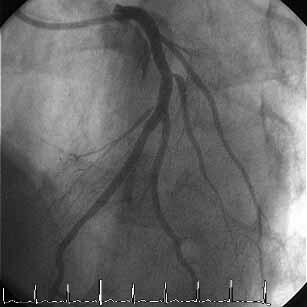

�͂��߂܂��āB���A�r58�N���̒��N��t�ł��B���͂܂��sRA�ł̃C���^�[�x���V����

�͖��o���ł��B�����~���L�b�g���łĂ���A�܂����ꂽfemoral�ł�������TFA�𑱂�

�Ă��܂������A��͂芳�҂���̖����x��radial���ォ�ȂƊ�����悤�ɂȂ�ATRA

��try���悤���Ǝv���͂��߂Ă��Ă��܂��B���낢��������Ē��������Ǝv���܂�

�̂ŁA��낵�����肢�������܂��B

�F����ɂ��ӌ��������Ǘ�̂o�b�h���s���܂����B

�VFr.TFI�A�K�C�h�J�e�W���h�L���X4.0�V���[�g�`�b�v

�P�ALAD�݂̂Ƀ��C���[�N���X���AIVUS�Ŋώ@�B

�Q�A�J���^���}�[�x���b�N4.5-8mm�ɂ�LMT�����v�����ADriver 4.0-9mm��I���B

�i�O�g���͂��Ă��Ȃ��j

�R�A�X�e���g���P�Q�C���Ŋg����AIVUS�B

�S�A�J���^���}�[�x���b�N4.5-8mm�Ō�g�����s���AIVUS�B

�T�A����ɃJ���^���}�[�x���b�N5.0-8mm�Ŋg����AIVUS���A�I���B